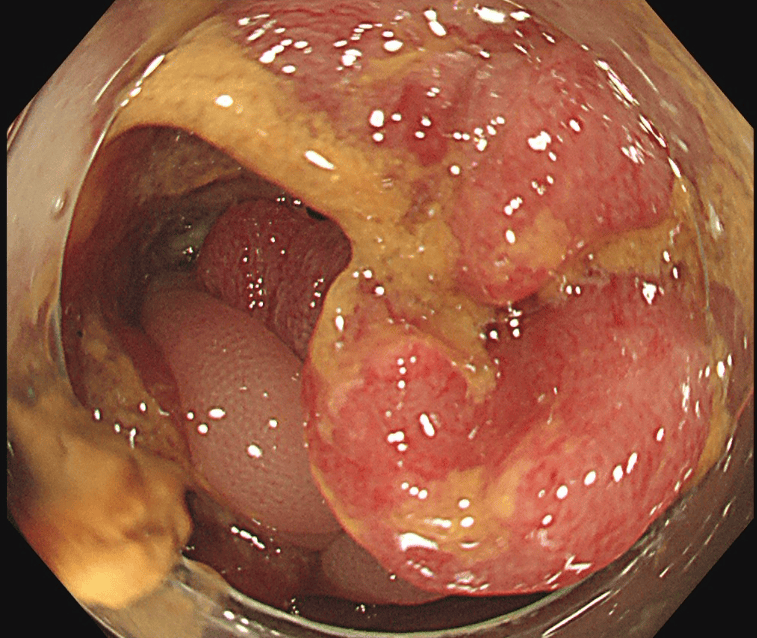

大腸がんに対してTNT療法を行った例

治療前